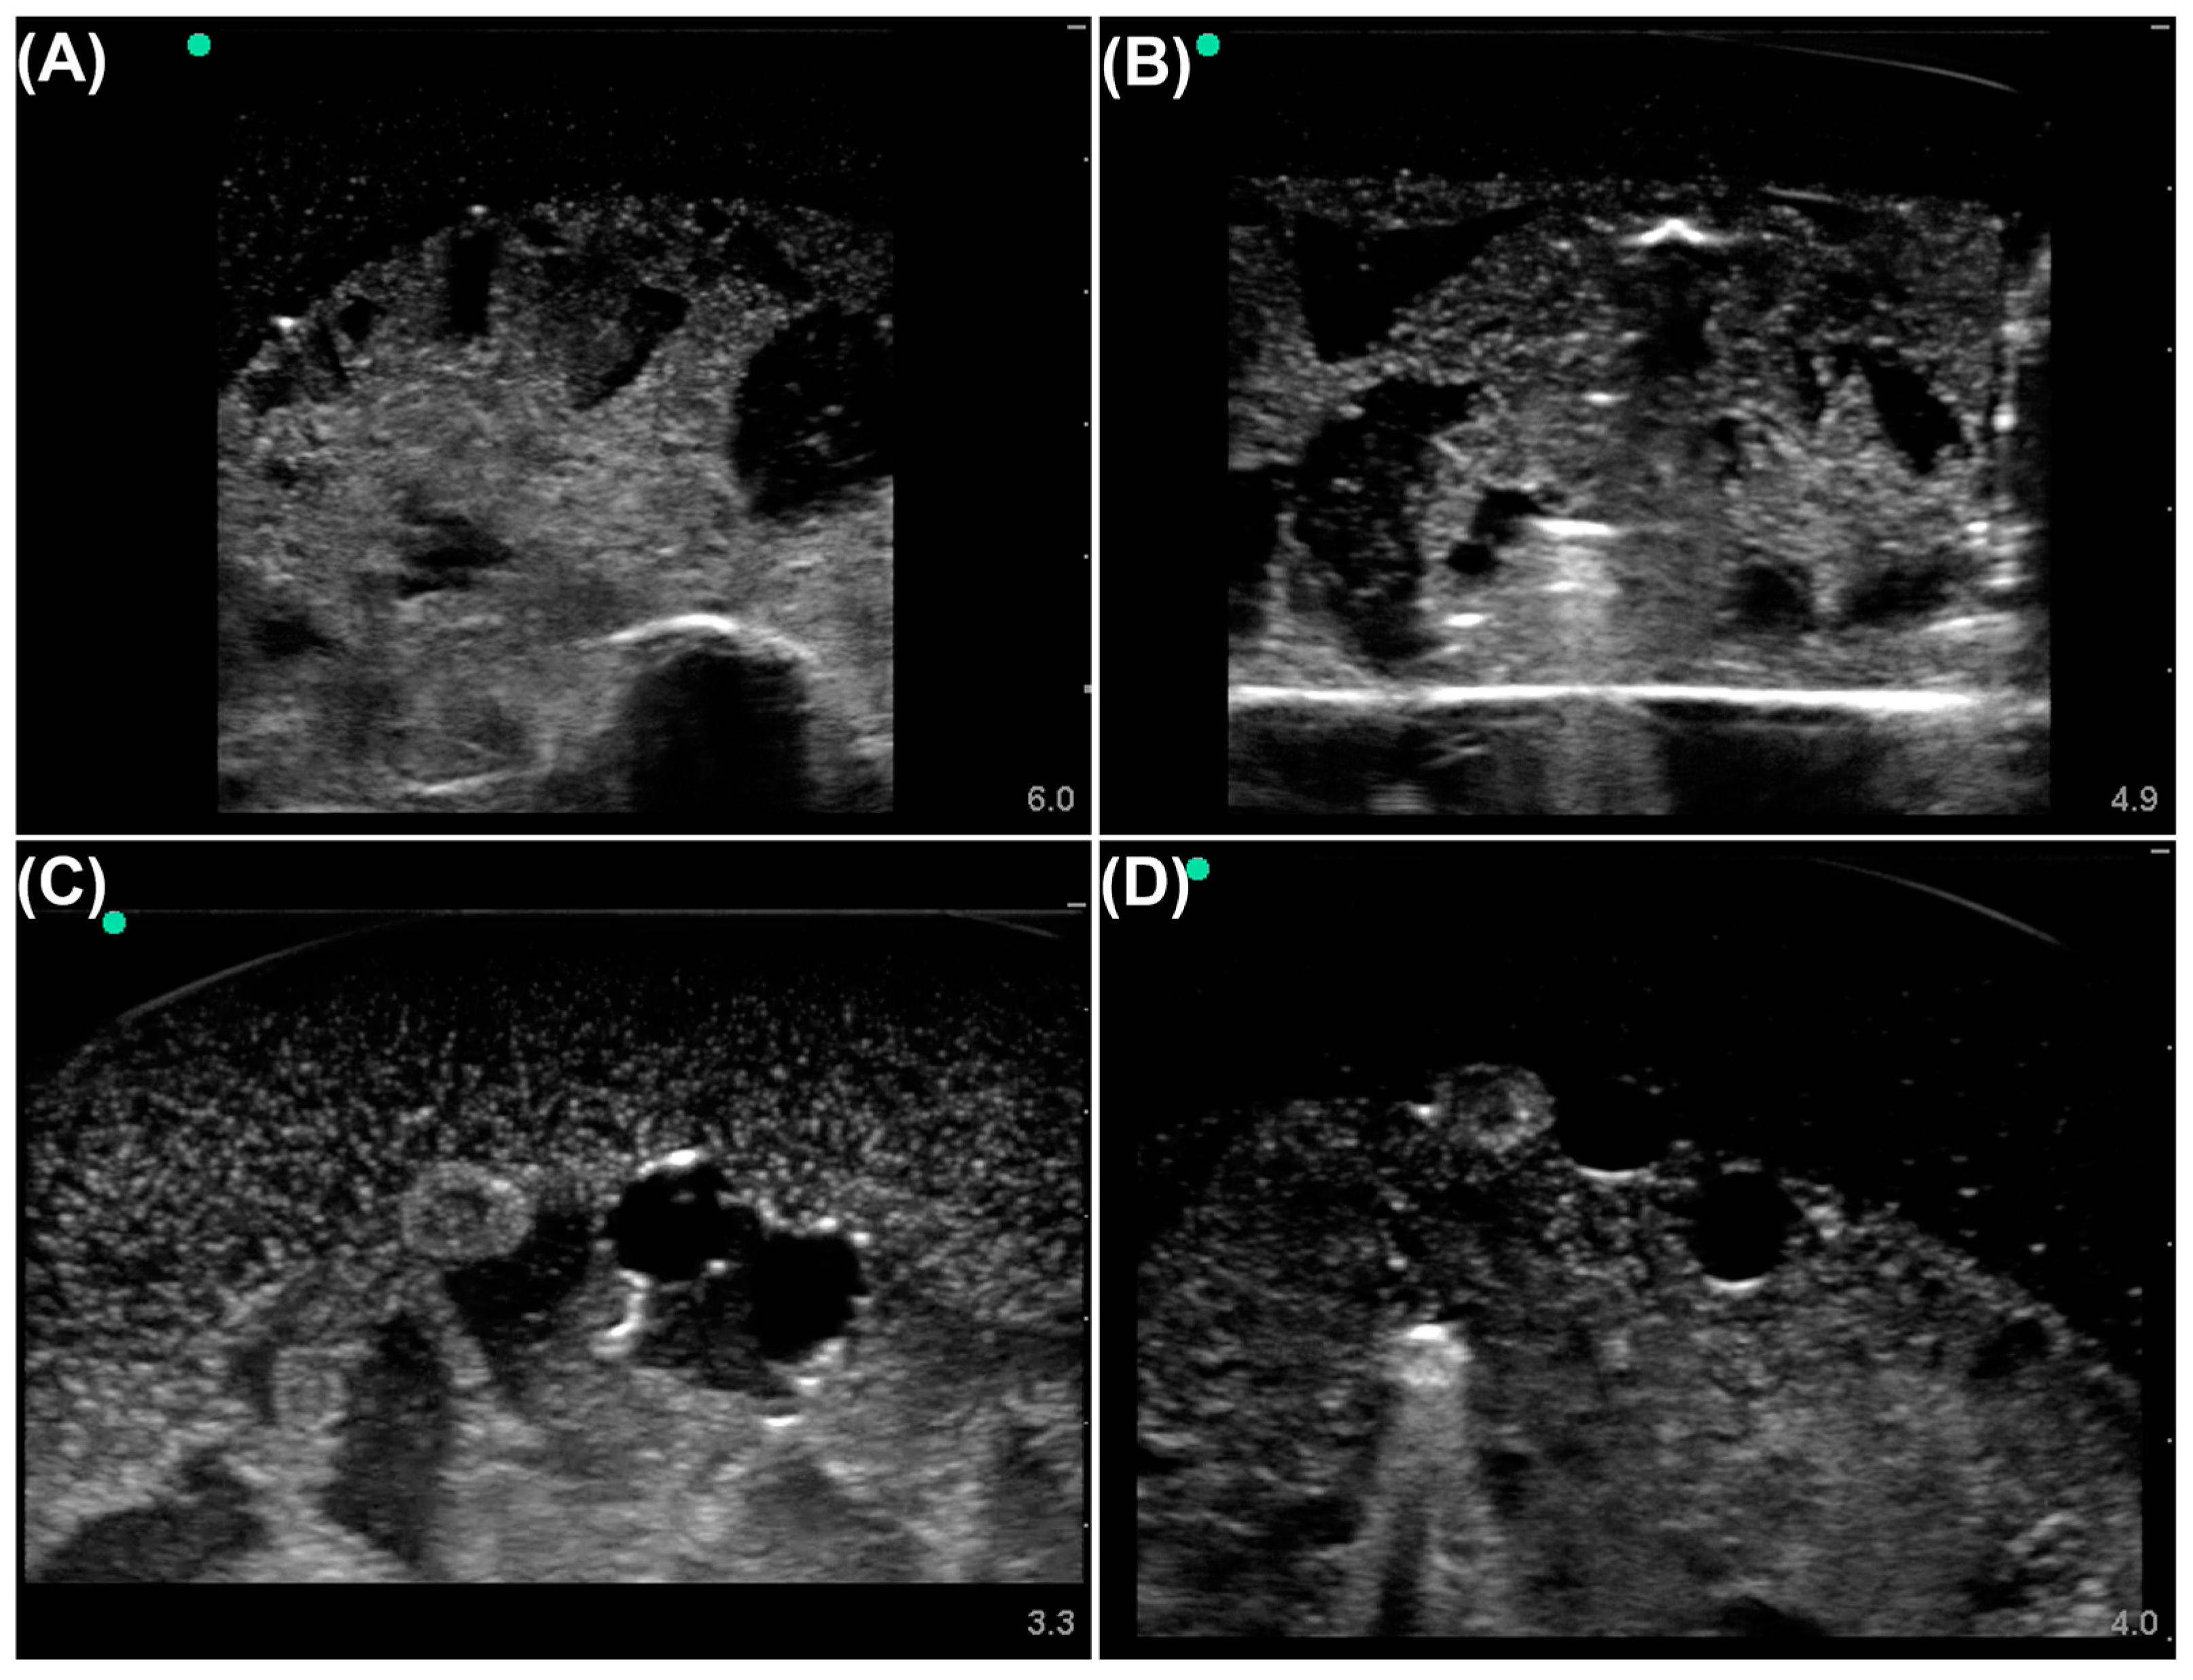

2.1. Dataset Prep